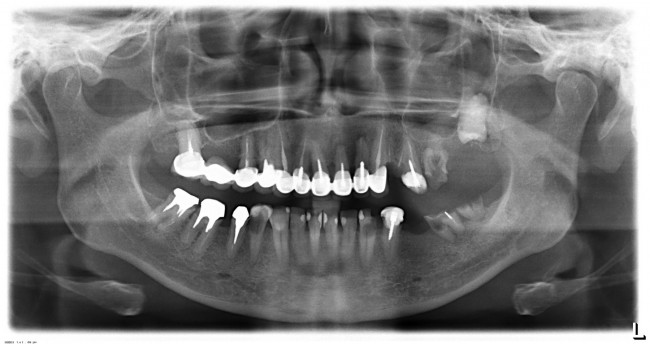

Вот пример. На этот раз, на снимках: пациентка, возрастом чуть больше сорока лет. После диагностики и необходимых исследований стало ясно, что необходимо хирургическое лечение во всех участках зубного ряда. В частности, удаление 13 зубов, включая ретинированный зуб мудрости, остеопластика на нижней челюсти и синуслифтинг, пластика слизистой и много чего еще.

Представьте, сколько времени займет хирургическая операция, если делать хотя бы половину этой работы за один раз? Как себя будет чувствовать пациентка во время и после хирургической операции? Как будет себя чувствовать доктор, какова вероятность критической усталости к концу операции? Как поддерживать анестезию и чистоту полости рта в течение такого длительного времени? И сколько будет стоить такая операция?

У меня нет ипотеки и других долгов, поэтому я принимаю решение разбить весь объем хирургического лечения на четыре этапа — по одному в каждом из сегментов зубного ряда. И начинаю я… угадайте, с какого участка? Верно, с того, который уже не функционален из-за критического разрушения зубов — с левого нижнего:

Операция заняла всего 60 минут, послеоперационные явления были настолько незначительны, что пациентка чуть ли не через пару недель решилась на вторую операцию:

Стоит ли сейчас приступать к третьему и четвертому этапам, а именно — к удалению зубов и имплантации на правой стороне? На мой взгляд, нет. И тут срабатывает принцип, поспешишь — людей насмешишь. Ну подумайте сами — у пациентки не интегрированы импланты с левой стороны, вся жевательная нагрузка приходится на правую сторону. Удалив зубы, мы сильно увеличим нагрузку на оставшиеся передние сегменты, которые, если честно, находятся не в лучшем состоянии. И это не говоря о том, как пациентка будет себя чувствовать, не имея возможности нормально пережевывать пищу. Поэтому в наших интересах — дождаться интеграции имплантов слева, установить на них временные протезы, перенести на них жевательную нагрузку, и только потом приступать к работе на правой стороне.